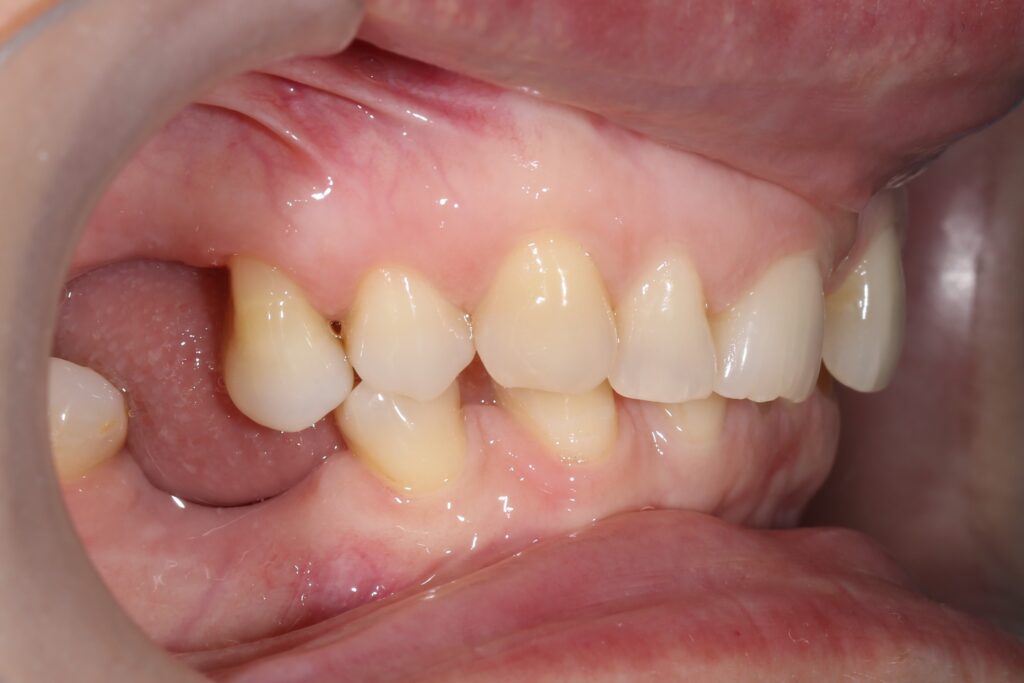

Ситуация до лечения

Из-за множественных давних удалений жевательных зубов, произошла деформация зубных рядов, зубы разъехались в область удаленных, что затрудняло протезирование в момент обращения к ортопеду.

Так же можно отметить сильное снижение высоты прикуса (верхние зубы на 100% перекрывали нижние, что вызывало хроническую травму десны), а также повышенную стираемость твердых тканей зубов, что является следствием повышенной нагрузки, которую много лет испытывали передние зубы, в связи с отсутствием жевательных зубов.